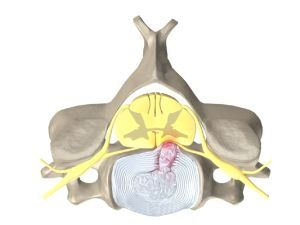

Радикулопатією називають патологію нервових корінців хребта, що беруть свій початок від спинномозкових нервів. Нервові корінці можуть бути ущемлені, що призводить до їх запалення і пошкодження.

В результаті відбувається зниження амортизаційних і еластичних властивостей, знос зовнішнього кільця і зменшення висоти між хребцями.

- По перше. тут спостерігається витончення міжхребцевих дисків, що призводить до випинання сегмента і його фіброзного кільця. В процесі дегенеративних змін гелевидний ядро диска випинається назовні - утворюється грижа.

- По-друге. міжхребетні диски дратують, а потім обмежують нервові спинномозкові закінчення. Диски вражають один або кілька корінців, які можуть бути розташовані в різних відділах хребта.

Вертеброгенна радикулопатия є вторинну форму прояви дискогенной різновиди. Якщо в першому випадку відбувалися зміни і наростання своєрідних «стінок» близько нервових корінців, то тепер ці нарости починають тиснути.